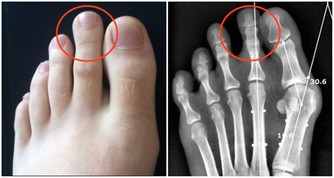

病程初期可出現活動後疼痛,休息後緩解。隨著壞死面擴大,胯部疼痛會加劇,持續壓痛,休息後不會緩解,嚴重影響生活。透過檢查可見X光股骨頭密度降低、塌陷。對於這種疾病的治療,專家建議以保守治療為主,也可依年齡選擇人工關節置換。

隨著軟骨變薄,關節活動範圍也逐漸限制,嚴重時可完全喪失功能。X光檢查可見關節間隙變窄、骨贅形成。而且病灶還多累及胯骨內側。在治療方面,臨床可採用物理治療、適度運動等保守治療。對於晚期嚴重者可選擇人工關節置換手術。